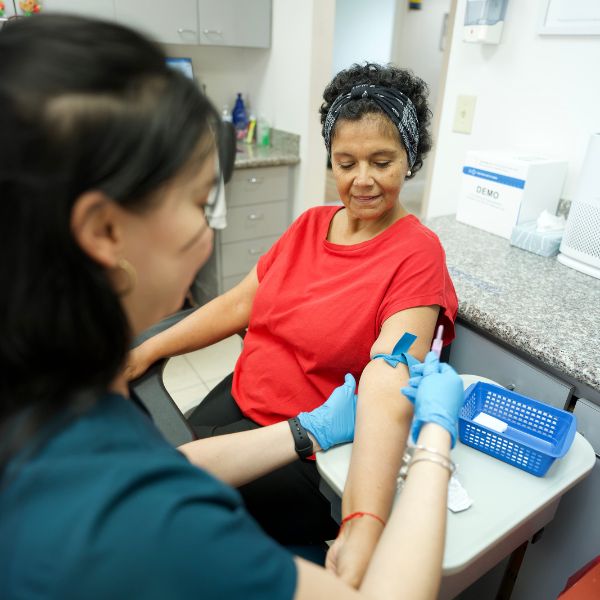

Laboratorio